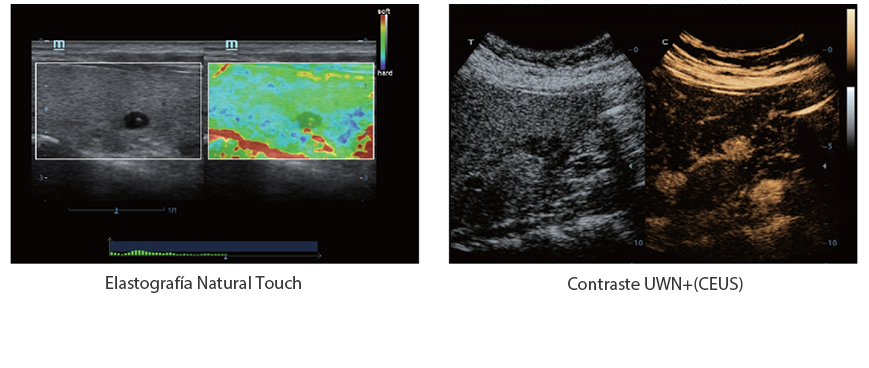

X-Insight es la soluci├│n intuitiva para una mejor visualizaci├│n.

La nueva soluci├│n de Mindray es una excelente transformaci├│n desde la continua comprensi├│n de las necesidades cl├Łnicas del usuario, combinada con la evoluci├│n de la tecnolog├Ła de los ultrasonidos m├Īs puntera. Repleto de vitalidad, con el ├║nico objetivo de visualizar el futuro y evitar los l├Łmites, el ec├│grafo DC-60Exp con X-Insight est├Ī constantemente mejorando con una escalabilidad aumentada. Como un socio personal, el equipo de ultrasonidos DC-60 Exp con X-Insight se centra en lo que verdaderamente importa, ayudando al usuario a administrar su pr├Īctica cl├Łnica con facilidad y seguridad.

Bas├Īndose en una profunda comprensi├│n de las necesidades del usuario, el sistema de ultrasonidos DC-60 Exp con X-Insight est├Ī dise?ado para ofrecer una alta eficiencia con im├Īgenes de precisi├│n, la cual se ve potenciada por una claridad inmediata, una inteligencia excepcional y benefici├Īndose de una c├│moda experiencia.